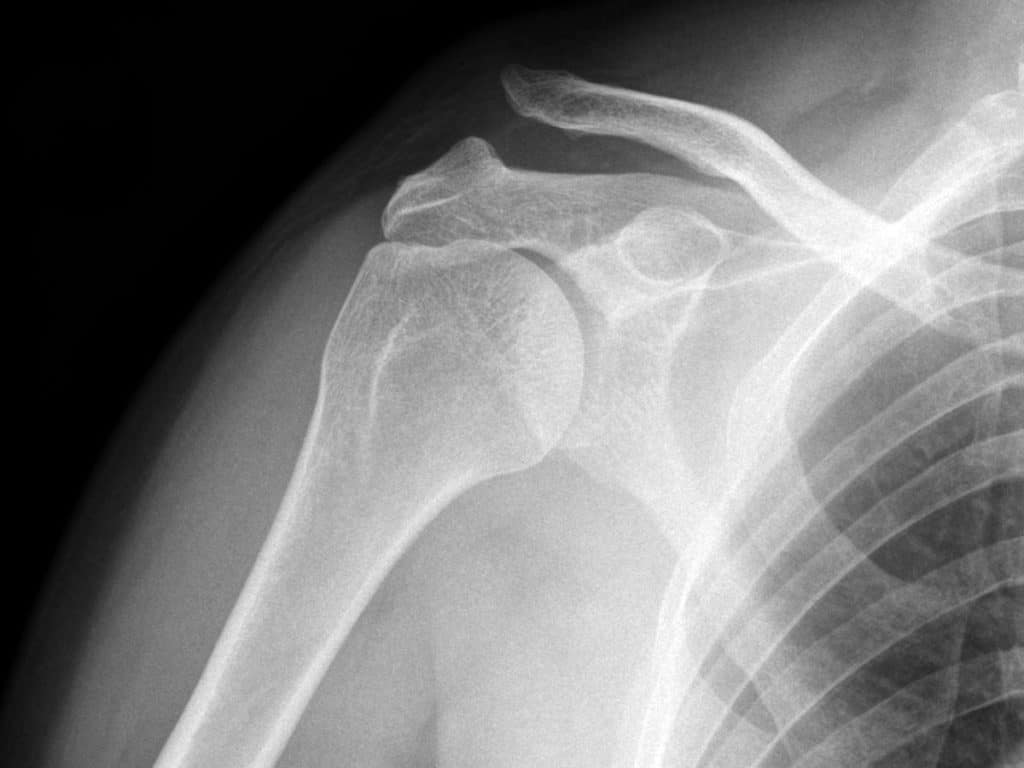

Диагноз вывиха акромиального конца ключицы

Диагноз вывиха акромиального конца ключицы иногда очень прост и все очевидно при осмотре, а иногда приходится решать целую головоломку. Наиболее оптимальным и распространенным способом диагностики является рентгенография. Стоит сказать, что, как не бывает одинаковых людей, так и не бывает одинаковых ключиц. Чаще всего причиной ложного диагноза индивидуальные особенности акромиально-ключичного сустава.

Поэтому целесообразно выполнять рентгенограмму не одного плеча, а двух сразу — что позволит оценить нормальное строение противоположной ключицы.

В сомнительных случаях иногда выполняют функциональную рентгенографию — в руку берут груз, который оттягивает ее вниз и вывих становится более очевидным.